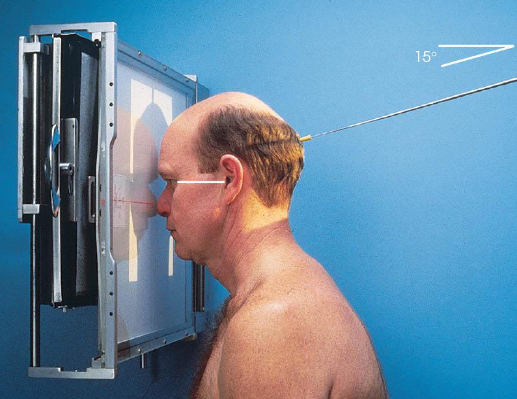

SMV (Schuller) skull

patient position:

upright (seated) or supine (torso elevated)

part position:

MSP centered to midline

MSP perpendicular to IR

IOML parallel with IR

patient hyperextends neck and rests head on vertex

respiration suspended

CR:

perpendicular through sella turcica and IOML

enters MSP of throat between angles of mandible (gonion)

passes through a point ¾ inch anterior to the level of the EAM

collimation:

½ inch beyond the shadow of the tip of the nose and 1 inch beyond the lateral borders